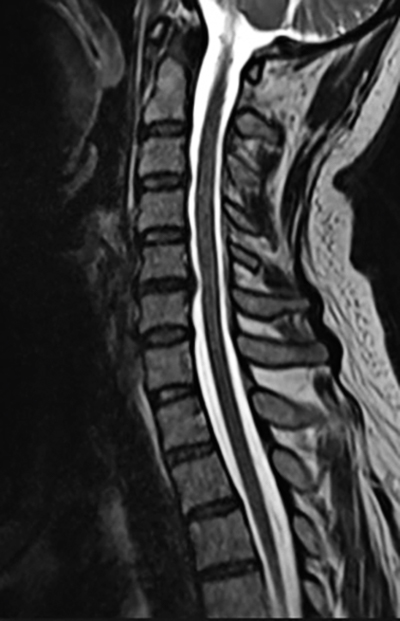

T2-viktad MR-bild med diskbuktningar och ligamentum flavum-hypertrofi som orsakar ryggmärgskompression C4/C5 samt C5/C6. Därutöver ses signalförändring i ryggmärgen på motsvarande nivåer.

MR-bild av halsrygg för jämförelse. Sagittalt snitt. En mindre diskbuktning ses C5/C6, men ingen kompression av ryggmärgen. Likvor (ljus vit färg) flödar fritt på båda sidor av ryggmärgen.